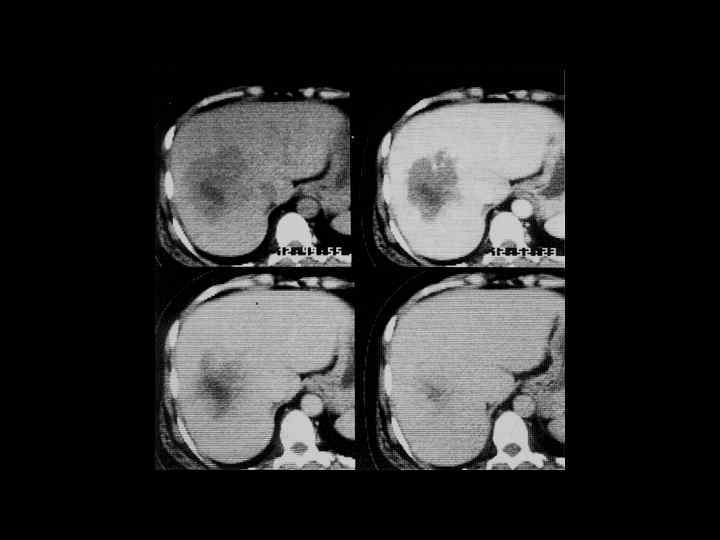

АКТУАЛЬНЫЕ ВОПРОСЫ РЕНТГЕНОЛОГИИ ЛУЧЕВАЯ ДИАГНОСТИКА ОЧАГОВЫХ ПОРАЖЕНИЙ ПЕЧЕНИ КАВЕРНОЗНАЯ ГЕМАНГИОМА Компьютерно-томографическая семиотика: - ограниченный участок пониженой плотности (до 50 -30 ед Н) - границы могут быть ровными, но нечеткими - после введения РКВ - характерный феномен усиления плотности от периферии к центру в течении нескольких минут после внутривенного введения РКВ

Клиническое наблюдение. Пациентка С. , 1953 г. р.

Та же пациентка